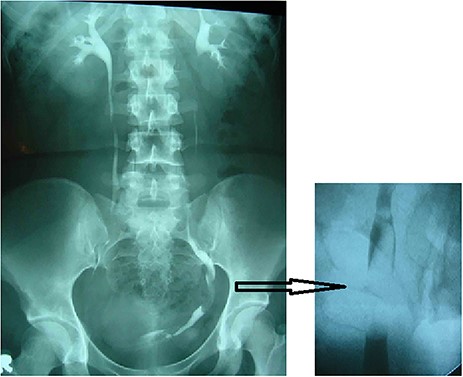

A post-operative excretory urogram revealed the presence of a distal left ureteral elongated regular non-obstructing filling defect (Fig. 3).

Excretory urogram (left) and RUPG (right) showing the distal left ureteral elongated regular non-obstructing filling defect.

A RUPG, under general anesthesia identified a floating filling defect starting approximately from the mid ureter (Fig. 3).